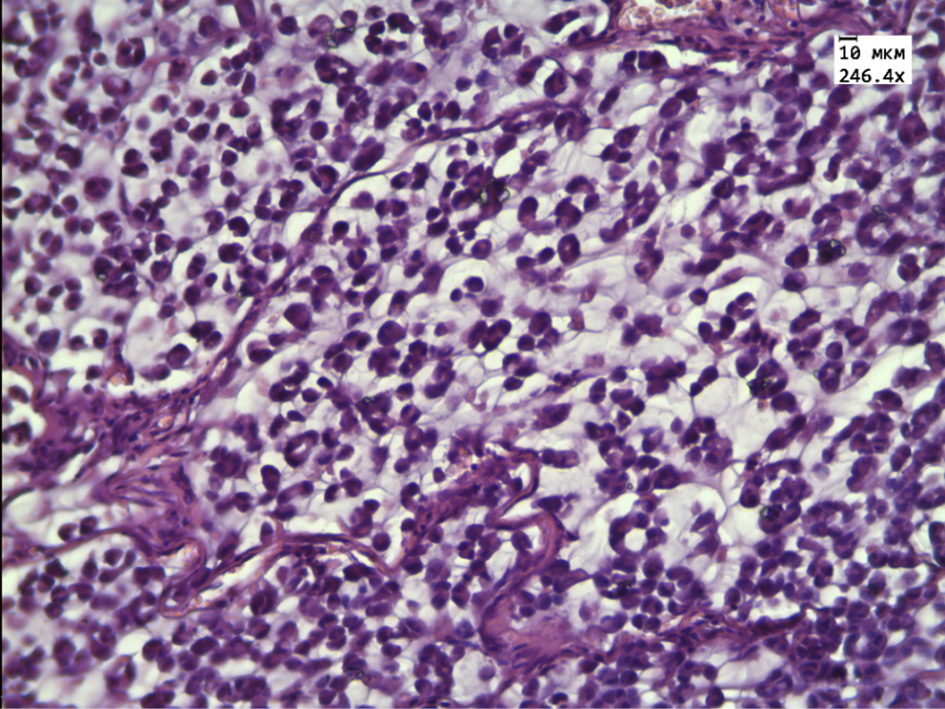

The morphological examination revealed that the transplanted tumor in the control group consisted of cellular structures of different shapes and sizes, separated by thin layers of connective tissue (Fig. 1). Tumor cells of oval or rounded shape, in the cytoplasm are large vacuoles containing mucus and pushing the oval nucleus to the periphery of the cell. The number of mitoses was 6 in one visual field. Single tumor cells of necrosis were noted.

Figure 1 – Histological tumor structure of the control group

Note: the tumor cells are separated by thin layers of connective tissue. Stained with hematoxylin and eosin. Magnification 246.4×.